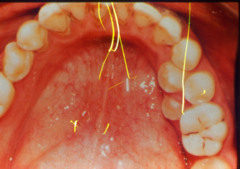

chronic hyperplastic pulpitis

-Red or pink nodule protruding from the pulp chamber or a tooth with a large open carious lesion (usually molars)